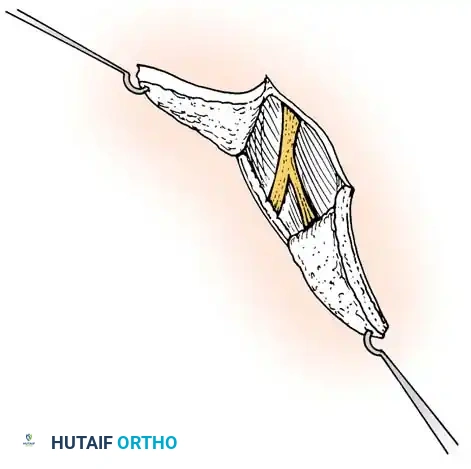

Fig. 76-3 A and B. Early fitting of a passive prosthesis in a child with a congenital forearm amputation is critical to encourage incorporation of the prosthesis into the child's body image.

1. 3 to 6 Months (Sit to Fit): A passive plastic mitten prosthesis is introduced once the child achieves independent sitting balance. This provides stability during sitting and assists in pulling to a stand.

2. 12 to 18 Months: The passive mitten is exchanged for an actively opened, plastisol-covered split hook. A Child Amputee Prosthetic Program (CAPP) terminal device may be substituted. Training with the functional device begins immediately.